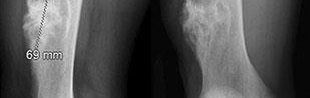

A 32-year-old male develops extreme pain out of proportion, pain with passive stretch, and tense compartments following a closed tibial shaft fracture. Which of the following best describes the fundamental pathophysiologic mechanism leading to cellular hypoxia and tissue death in acute compartment syndrome?

Explanation

The pathophysiology of compartment syndrome is driven by an increase in interstitial tissue pressure within a closed non-yielding fascial space. As tissue pressure rises, it quickly surpasses the low capillary venous pressure, severely impairing venous outflow. This leads to a decreased arteriovenous (AV) pressure gradient, resulting in diminished local capillary blood flow, capillary collapse, ischemia, and subsequent muscle/nerve necrosis. Arterial inflow is typically maintained until very late, which is why pulses are usually palpable even in established compartment syndrome.